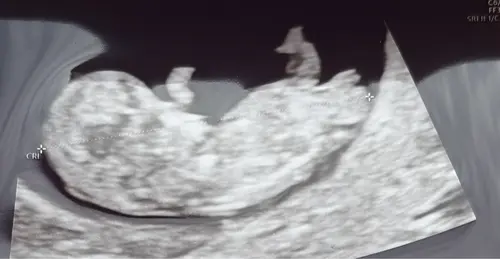

Het is dan met meer zekerheid vast te stellen, maar op basis van de nub-theorie wordt vaak geprobeerd om rond 12–14 weken zwangerschap het geslacht te voorspellen door te kijken naar de hoek van het zogenaamde “nub” (het uitsteeksel waaruit later de geslachtsdelen ontwikkelen):

< 30° t.o.v. de ruggengraat is vaak meisje.

> 30° t.o.v. de ruggengraat is vaak jongen

Ik zie denk ik een jongen

En dat komt doordat het nubje naar mijn idee meer omhoog steekt, maargoed.. dit bied geen officiële garantie 🤭